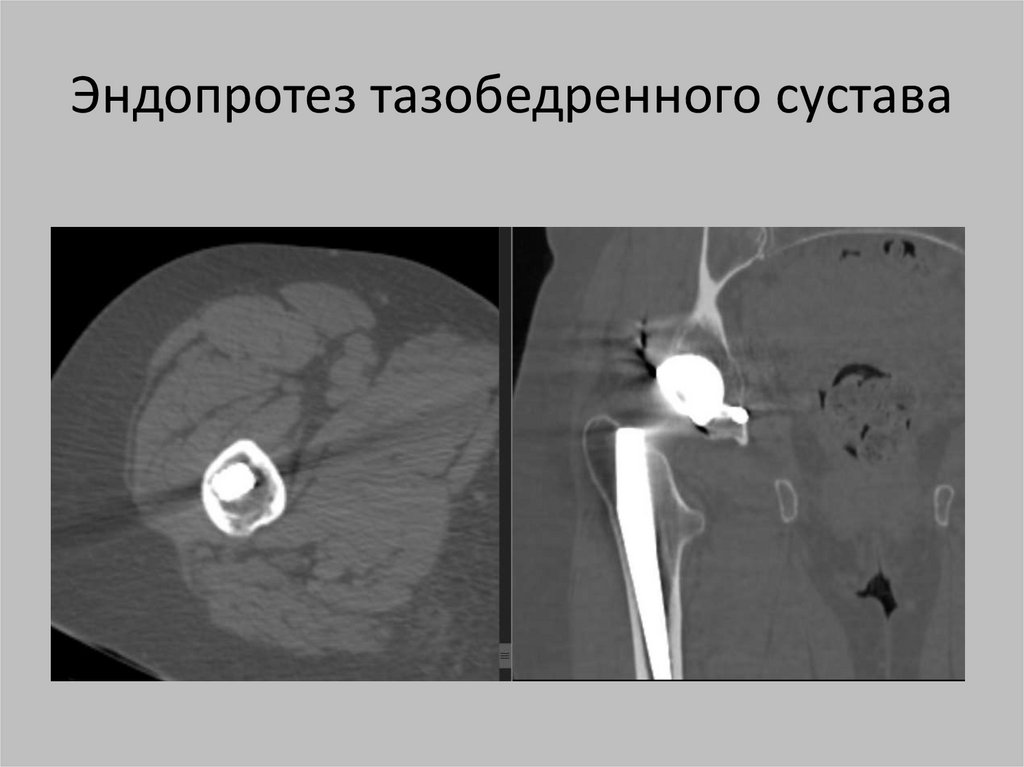

Эндопротез тазобедренного сустава